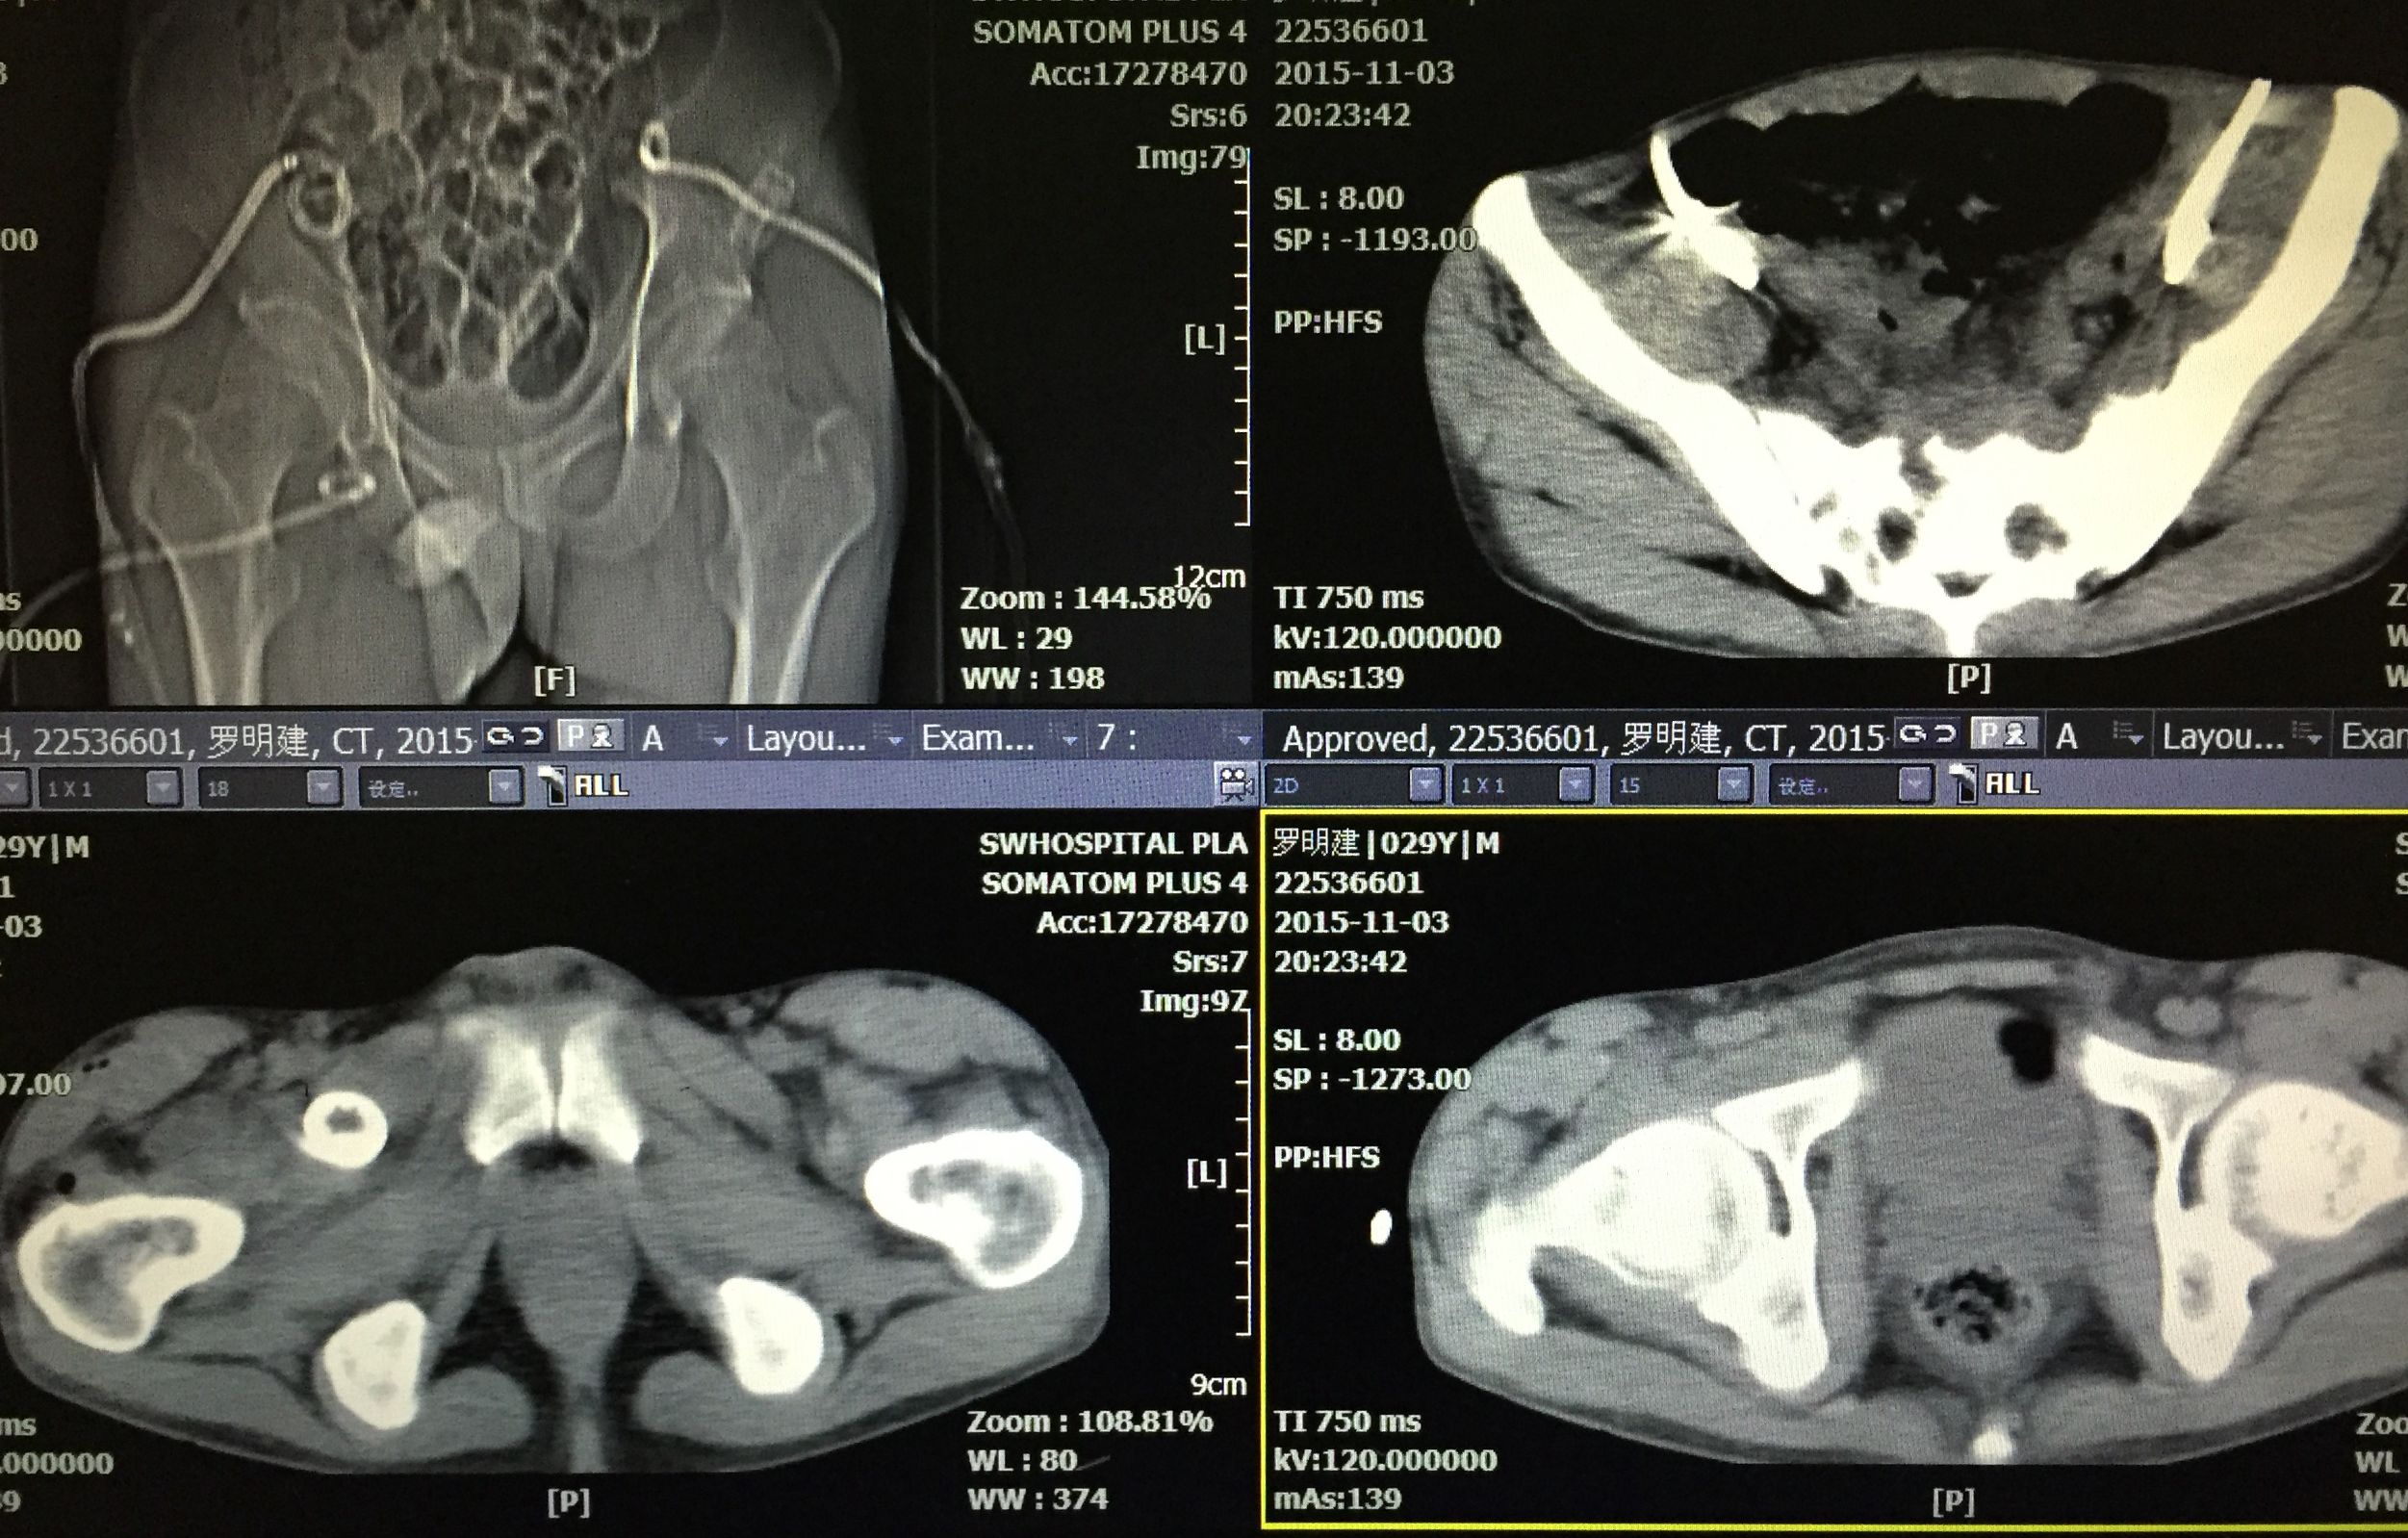

患者 29岁 盆腔及大腿根部多发结核脓肿(如图)

治疗方案充分穿刺置管引流+抗痨治疗

在门诊进行CT引导下穿刺引流术,植入五根引流管(如图白色条状物)

植入一月后,拔出两个引流管,剩余三根引流管仍有脓液溢出。

三月后患者全部拔出引流管。继续抗痨治疗